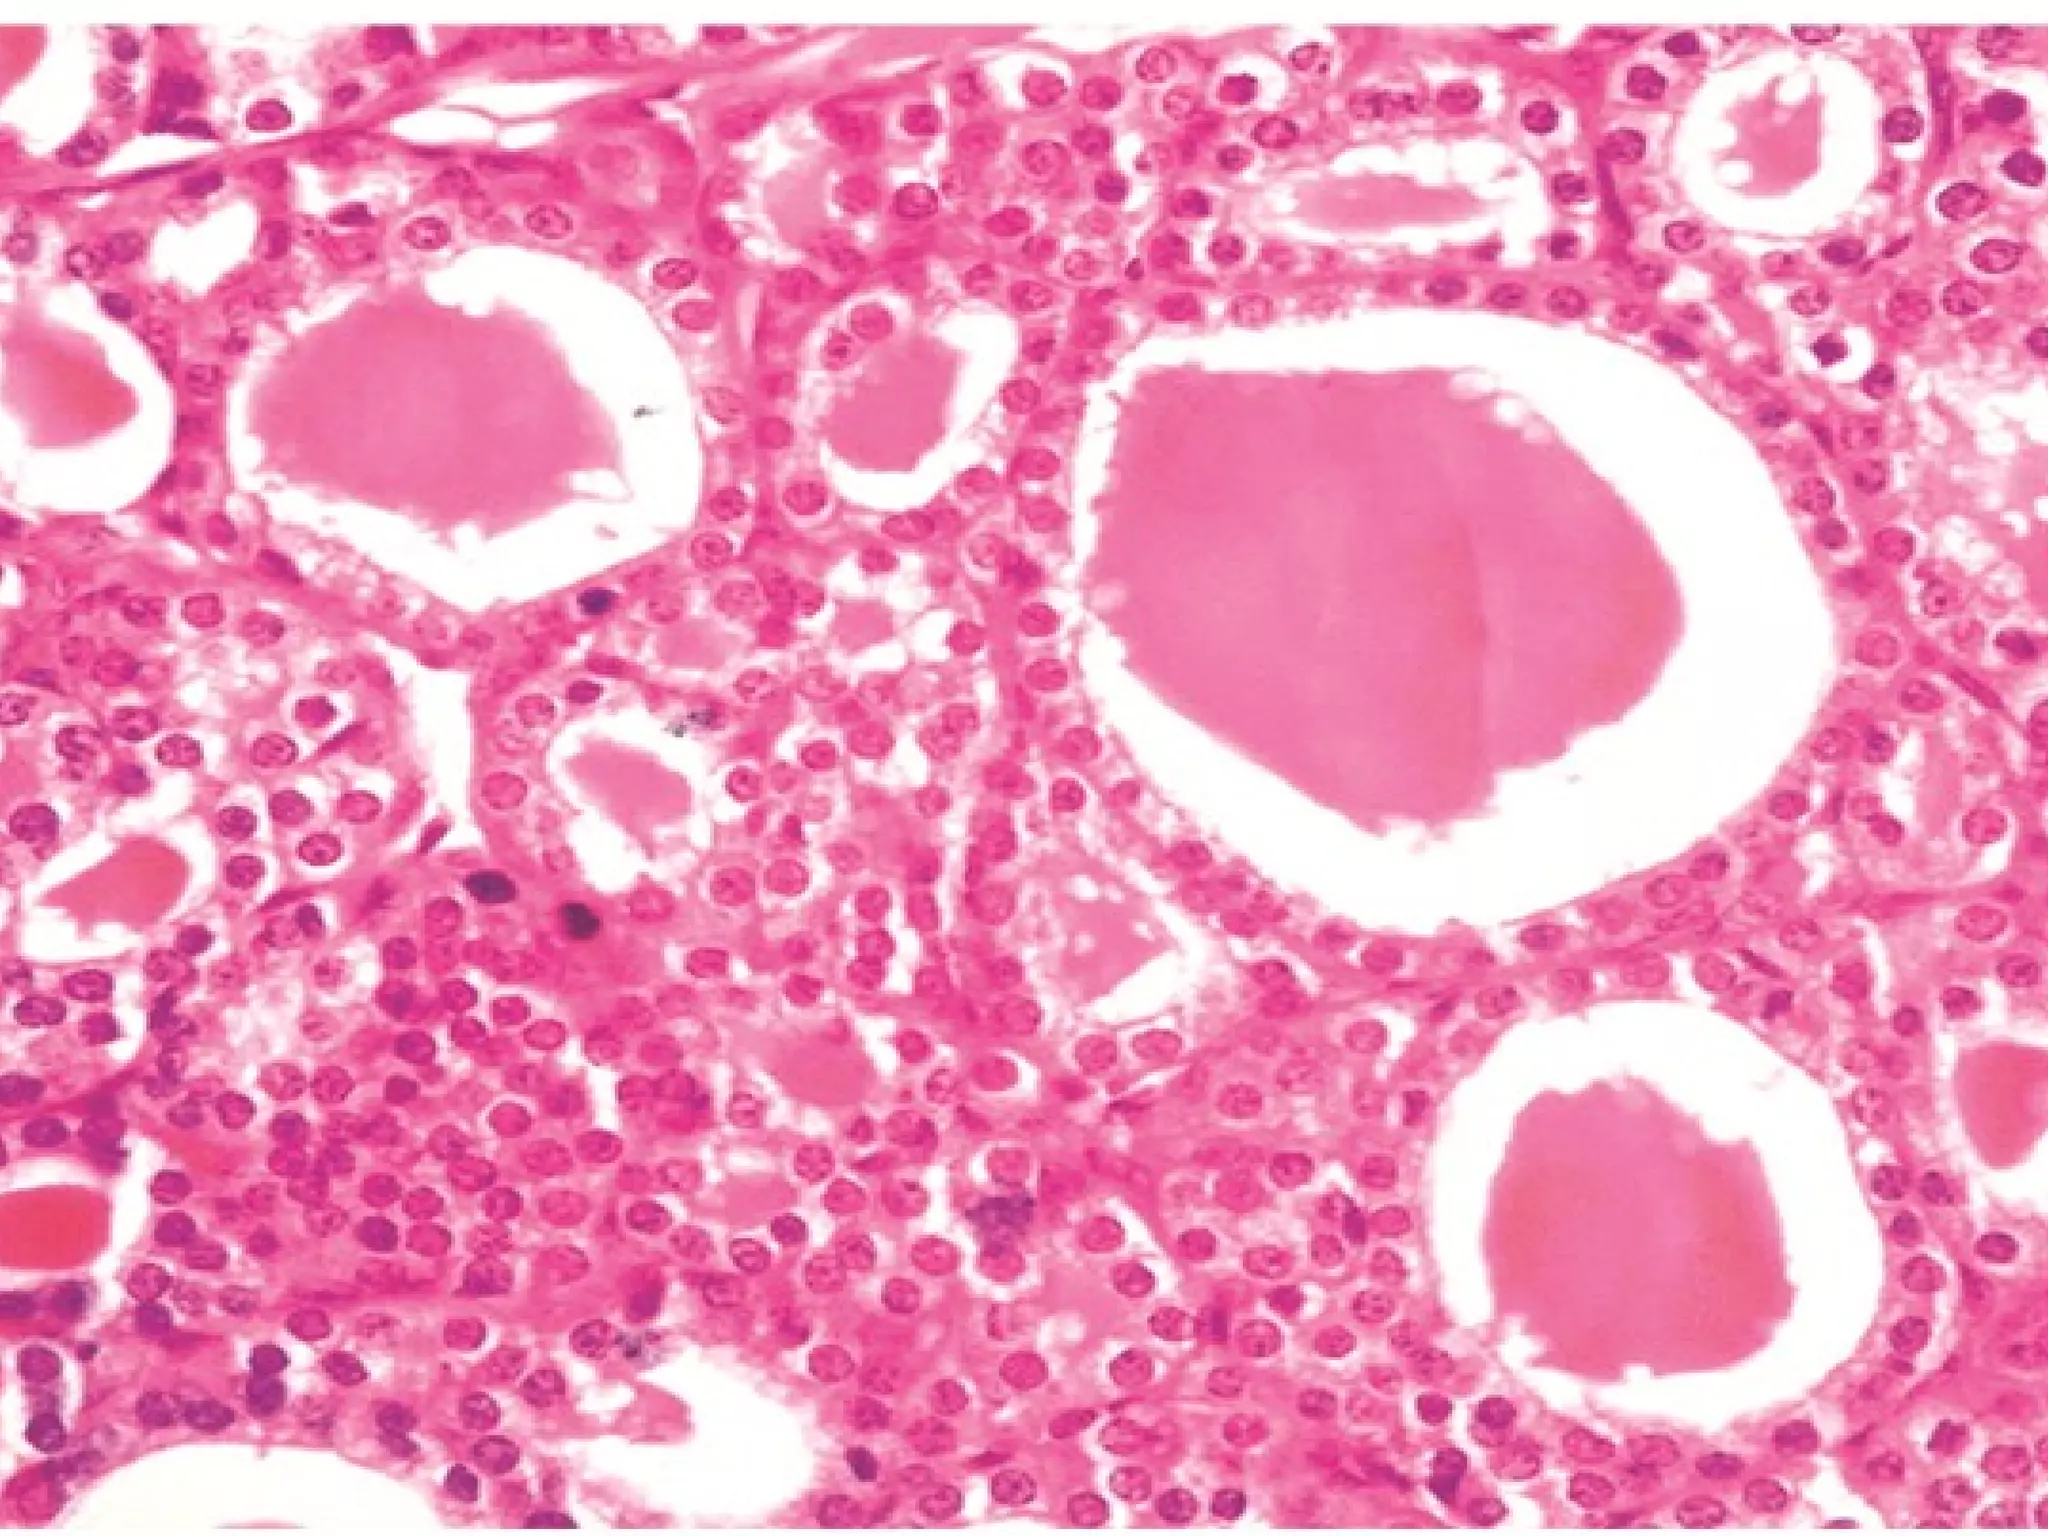

This document outlines several human body systems including the vascular, lymphatic, respiratory, digestive, and endocrine systems. It describes the trachea and lungs in the respiratory system, the oral cavity and digestive glands in the digestive system, and mentions the parotid, pancreas, and classic hepatic lobule in relation to the digestive system and endocrine glands.